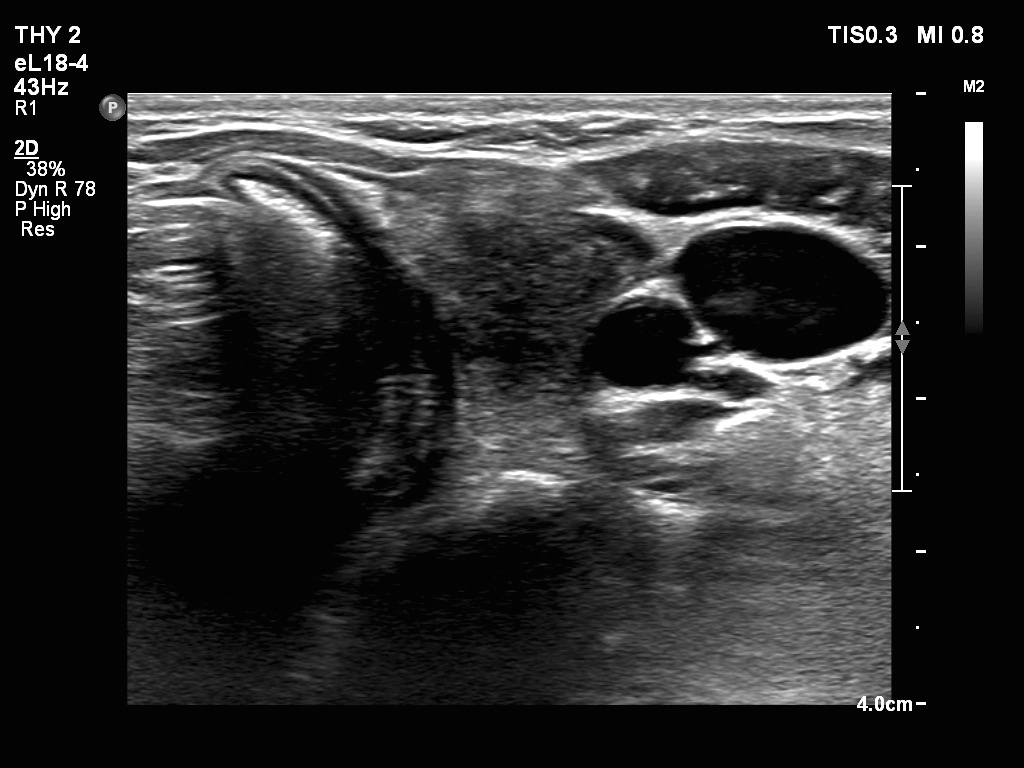

Ultrasonography. The thyroid was echonormal. There were two nodules in the right lobe. The upper was hyperechogenic-cystic while the lower was a minimally-moderately hypoechogenic. The latter had irregular, lobulated margins. There was a hypoechoic area in the upper two-third of left lobe. The discrete area presented ill-defined margins and decreased vascularization. A spongiform cyst was found in the lower pole of the left lobe.